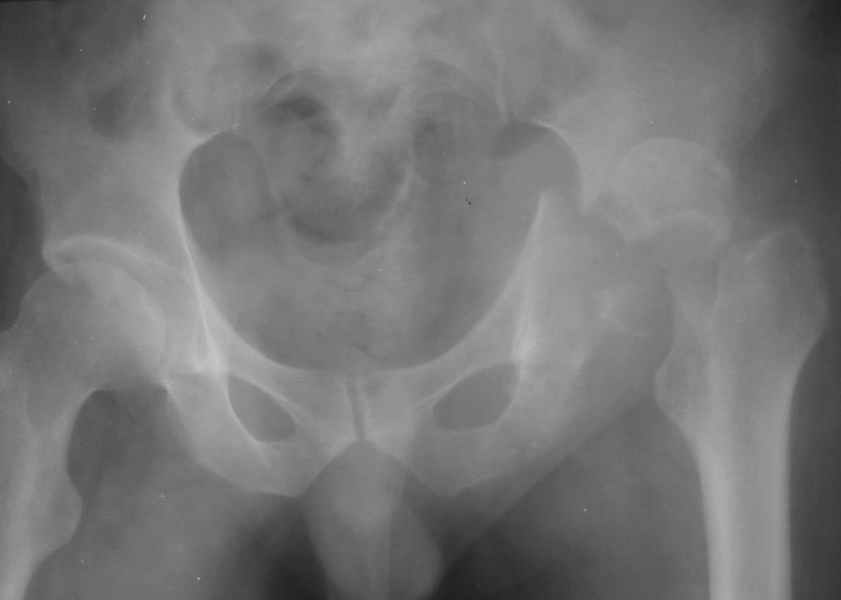

Дорогие коллеги, Поступил пациент, 5 месяцев, как сломался.

Поступил для эндопротезирования, но наши корифеи засомневались, не собрать ли сначала таз. Есть ли смысл собирать аппаратом закрыто?

Вариант с постепенной репозицией возможен, у нас такие операции были - аппаратом с введением стержней через вертельную зону в лонно-седалищный фрагмент с подтягиванием его латерально и дистально до максимального контакта задней колонны, затем открытый остеосинтез впадины с заполнением дефекта всем, чем попало. Через 2-3 мес. - эндопротез стандартным доступом, делали винтовую чашку.

Однако, учитывая вывих, 5-месячный срок мы бы, наверно, без аппарата сразу забрались в сустав с целью его реконструкции и остеосинтеза винтами и пластинами. Если удастся сделать остеосинтез хорошо - сразу сделать и эндопротез. Доступ - есссно, не как на протез, а как на впадину - или Y-образный с остеотомией болшого вертела, или латеральный. В случае подозрения на нестабильность впадины после остеосинтеза или больших трудностей при синтезе - засунуть головку во впадину, сделать остеосинтез шейки винтами, и дождаться сращения впадины, попытавшись сохранить движения в суставе. Пишут, можно противопротрузионными кольцами или Octopus укрепить остеосинтез впадины, и тогда тоже делать протез сразу, но у нас такого опыта нет, в основном предпочитали делать в два этапа - сначала реконструкция впадины, потом протез, потому что в застарелых случаях впадина сильно кривая.

Здравствуйте. Разрешите предложить вам следующий вариант: Доступ- задний типа Кохера, с возможным отсечением большого вертела. Репозиция поперечного перелома впадины (насколько возможна), остеосинтез реконструктивной пластиной. В случае большого деффекта заднего края и крыши- пластика фрагментом головки бедра. Ацетабулярный компонент- реконструктивное кольцо. Есть вариант одномоментного остеосинтеза впадины на кольце типа Bursch-Shneider с фиксацией дистального лепестка кольца к седалищной кости.Желаю успехов.

Поэтому скорее всего я бы планировал открытую репозицию и фиксацию перелома впадины илеофеморальным или задним доступом с одномоментным протезированием( укрепляющее кольцо + бесцементный бедренный компонент).